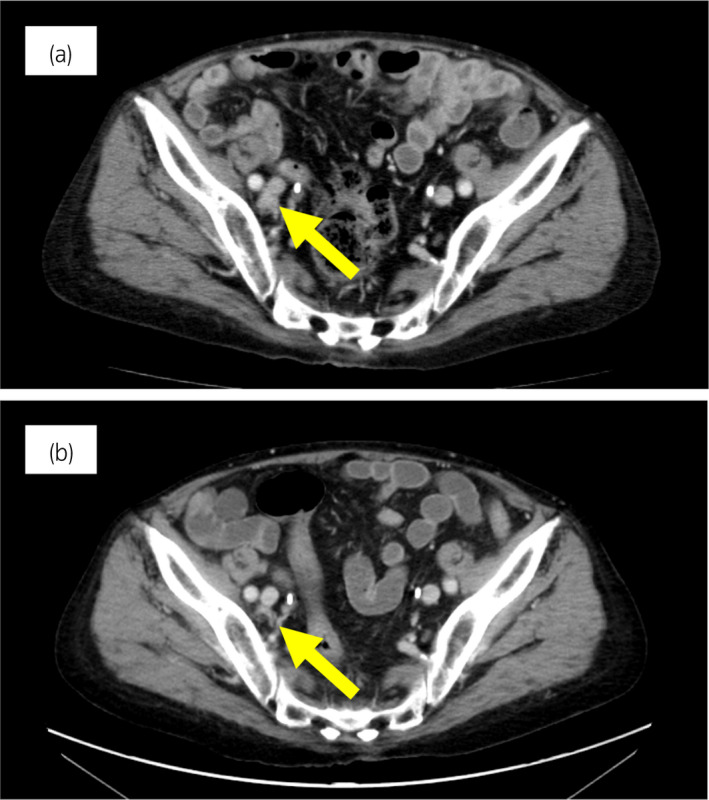

圖 4:病例 2:奧拉帕尼治療前和治療后 3 個月的盆腔淋巴結(jié) CT 圖像。 (a) 治療前和 (b) 奧拉帕尼治療后 3 個月。 黃色箭頭顯示轉(zhuǎn)移淋巴結(jié)。